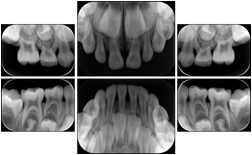

Intra-oral radiography typically involves acquisition of multiple images of various parts of the dentition. Many digital radiographic systems offer customized templates that are used for displaying the images in a study on the screen. These templates may also be referred to as mounts or view sets. The Structured Display Object represents a standard method of encoding and exchanging the layout and intended display of Structured Displays. A structured display object created in this manner could be stored with a study and exchanged with images to allow for complete reproduction of the original exam.

In most standard cases, images are oriented in structured layouts. These structured displays are useful to be shared between providers for reference purposes.

Table OO.1.1-1 shows structured display standard templates, where Viewset ID is based on the Japanese Society for Oral and Maxillofacial Radiology (JSOMR) classification provided by JIRA (Japan Medical Imaging and Radiological Systems Industries Association, www.jira-net.or.jp). Expected or typical teeth to be imaged location, region and designation codes are based on ISO 3950-2010, Dentistry - Designation system for teeth and areas of the oral cavity. For all the hanging protocols listed in OO.1.1-1, the value to use for Hanging Protocol Creator (0072,0008) is "JSOMR" and the value to use for Hanging Protocol Name (0072,0002) does not include "JSOMR" (e.g., "DL-S001A", not "JSOMR DL-S001A").